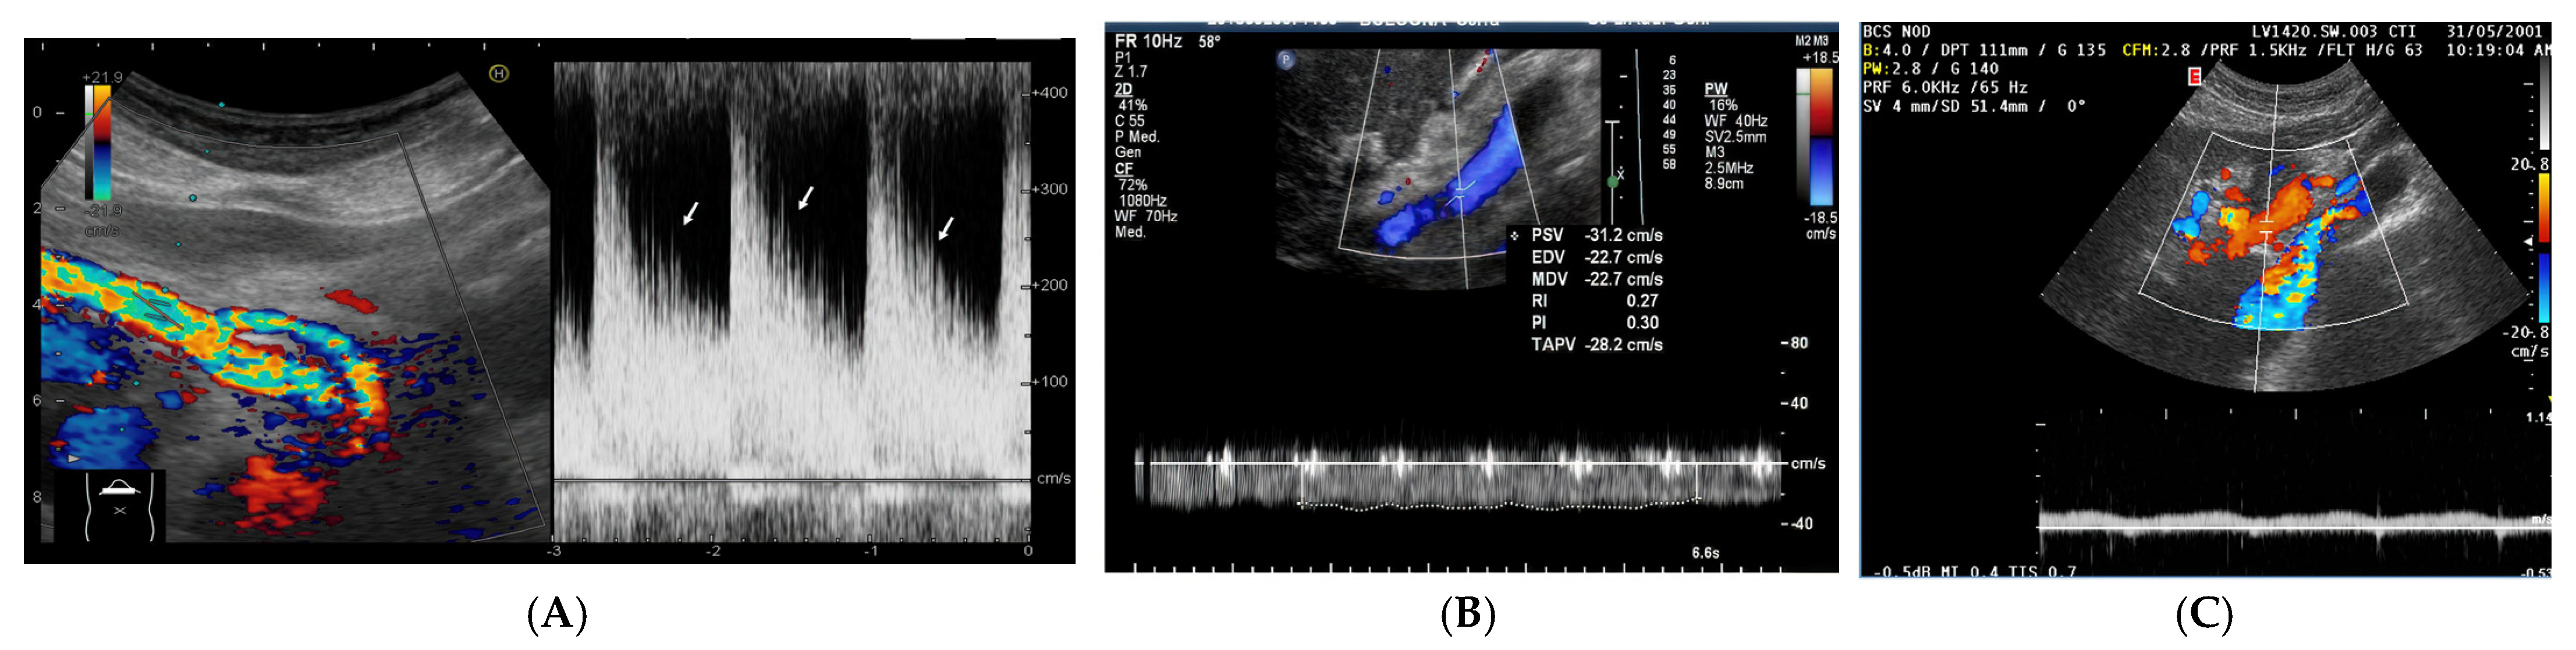

- 1.

- Increased Pulsatility (Pulsatile Waveform): A pulsatile portal venous flow occurs when there is a significant difference between peak systolic and end-diastolic velocities. This is due to abnormal transmission of pressure through the hepatic sinusoids, often caused by conditions like tricuspid regurgitation, right-sided heart failure (CHF), or arteriovenous shunting (as seen in cirrhosis or hereditary haemorrhagic telangiectasia (Figure 9A) [105]. Pulsatility can be differentiated clinically, with right-sided CHF and tricuspid regurgitation identifiable through the hepatic venous waveform and grayscale US showing dilated hepatic veins, unlike in cirrhosis, where hepatic veins are compressed.

- Slow Portal Venous Flow: Slow flow occurs when back pressure restricts forward flow, typically indicating portal hypertension. In these cases, peak velocity is less than 16 cm/s [106]. Causes of portal hypertension include cirrhosis, portal vein thrombosis (prehepatic), and right-sided heart failure (posthepatic). The most specific findings include the development of portosystemic shunts (like a recanalized umbilical vein) and slow or reversed (hepatofugal) flow.

- Hepatofugal (Retrograde) Flow: Hepatofugal flow happens when the pressure in the portal vein exceeds that of the liver, causing flow to reverse and appear below the baseline. This is another indicator of portal hypertension, which can be caused by various conditions, including cirrhosis, right-sided heart failure and other portal vein obstructions [107] (Figure 9).Figure 9. (A) Increased pulsatility due to arteriovenous shunting in a case of hereditary haemorrhagic telangiectasia; (B) Reduced Portal Flow in a case of cirrhosis (C) Hepatofugal Flow of Portal Vein is a late sign of Portal Hypertension. It happens when the pressure in the portal vein exceeds that of the liver, causing flow to reverse and appear below the baseline. This is another indicator of portal hypertension, which can be caused by various conditions, including cirrhosis, right-sided heart failure and other portal vein obstructions.Figure 9. (A) Increased pulsatility due to arteriovenous shunting in a case of hereditary haemorrhagic telangiectasia; (B) Reduced Portal Flow in a case of cirrhosis (C) Hepatofugal Flow of Portal Vein is a late sign of Portal Hypertension. It happens when the pressure in the portal vein exceeds that of the liver, causing flow to reverse and appear below the baseline. This is another indicator of portal hypertension, which can be caused by various conditions, including cirrhosis, right-sided heart failure and other portal vein obstructions.